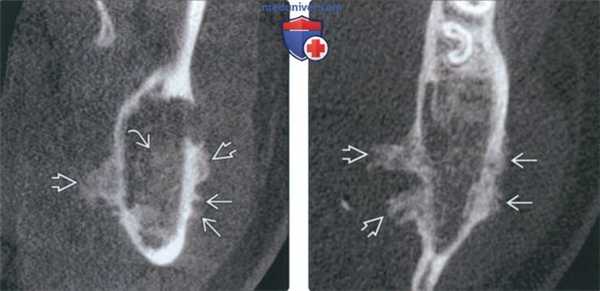

(Слева) На кадрированной панорамной рентгенограмме в задних отделах нижней челюсти слева определяется хорошо отграниченная остеосаркома. Формирующийся 3-й моляр ротирован и мезиально смещен опухолью, занимающей значительную часть угла и ветви нижней челюсти.

(Справа) На панорамной реформатированной КЛКТ у этого же пациента визуализируются кальцинаты в виде «дуг» и «завитков» с просветлениями в центре. Эти характерные признаки помогают отличить ХС от остеосаркомы, которая может выглядеть аналогично.

(Слева) На КЛКТ (профильный срез) у этого же пациента визуализируются периостальные наложения, расположенные перпендикулярно кортикальным пластинкам (в виде лучей), а также напластования вновь образованной костной ткани большею размера со стороны щечной и язычной поверхности. В опухоли присутствуют едва различимые кальцинатыв.

(Справа) На аксиальной КЛКТ у этого же пациента определяются периостальные наслоения вновь сформированной костной ткани, расположенные перпендикулярно щечной и язычной кортикальным пластинкам, более выраженные с язычной стороны.